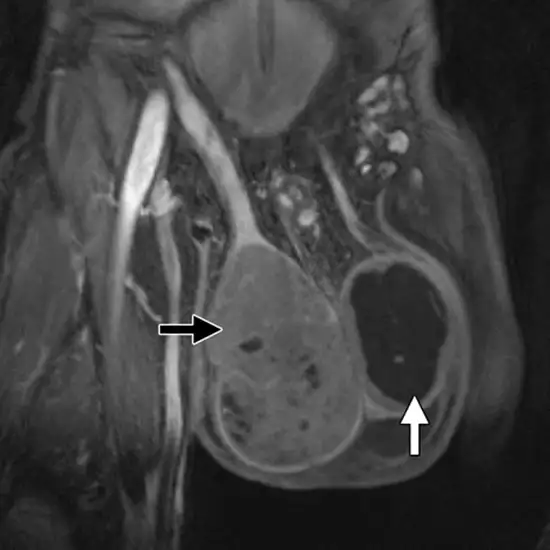

Every time there is a growth in the scrotal area, or, to put it simply, the sac that contains the testis, experts advise conducting this investigation. The different male genital organs that are located in the scrotum can be best seen on an MRI of the scrotal sac.

Therefore, MRI Screening scrotum is crucial for problems involving the male genital organs.

The following conditions can be easily detected using it:

• The Scrotum Has Lesions.

• In The Scrotum, Cysts

• Epididymis-Related Cysts

• Due To Genital Injuries, There Is Blood In The Scrotum.

• Testicular Tumours.

• Disease Of the Scrotum

• A Testicular Infection

• Multiple Testicles

• Lipoma